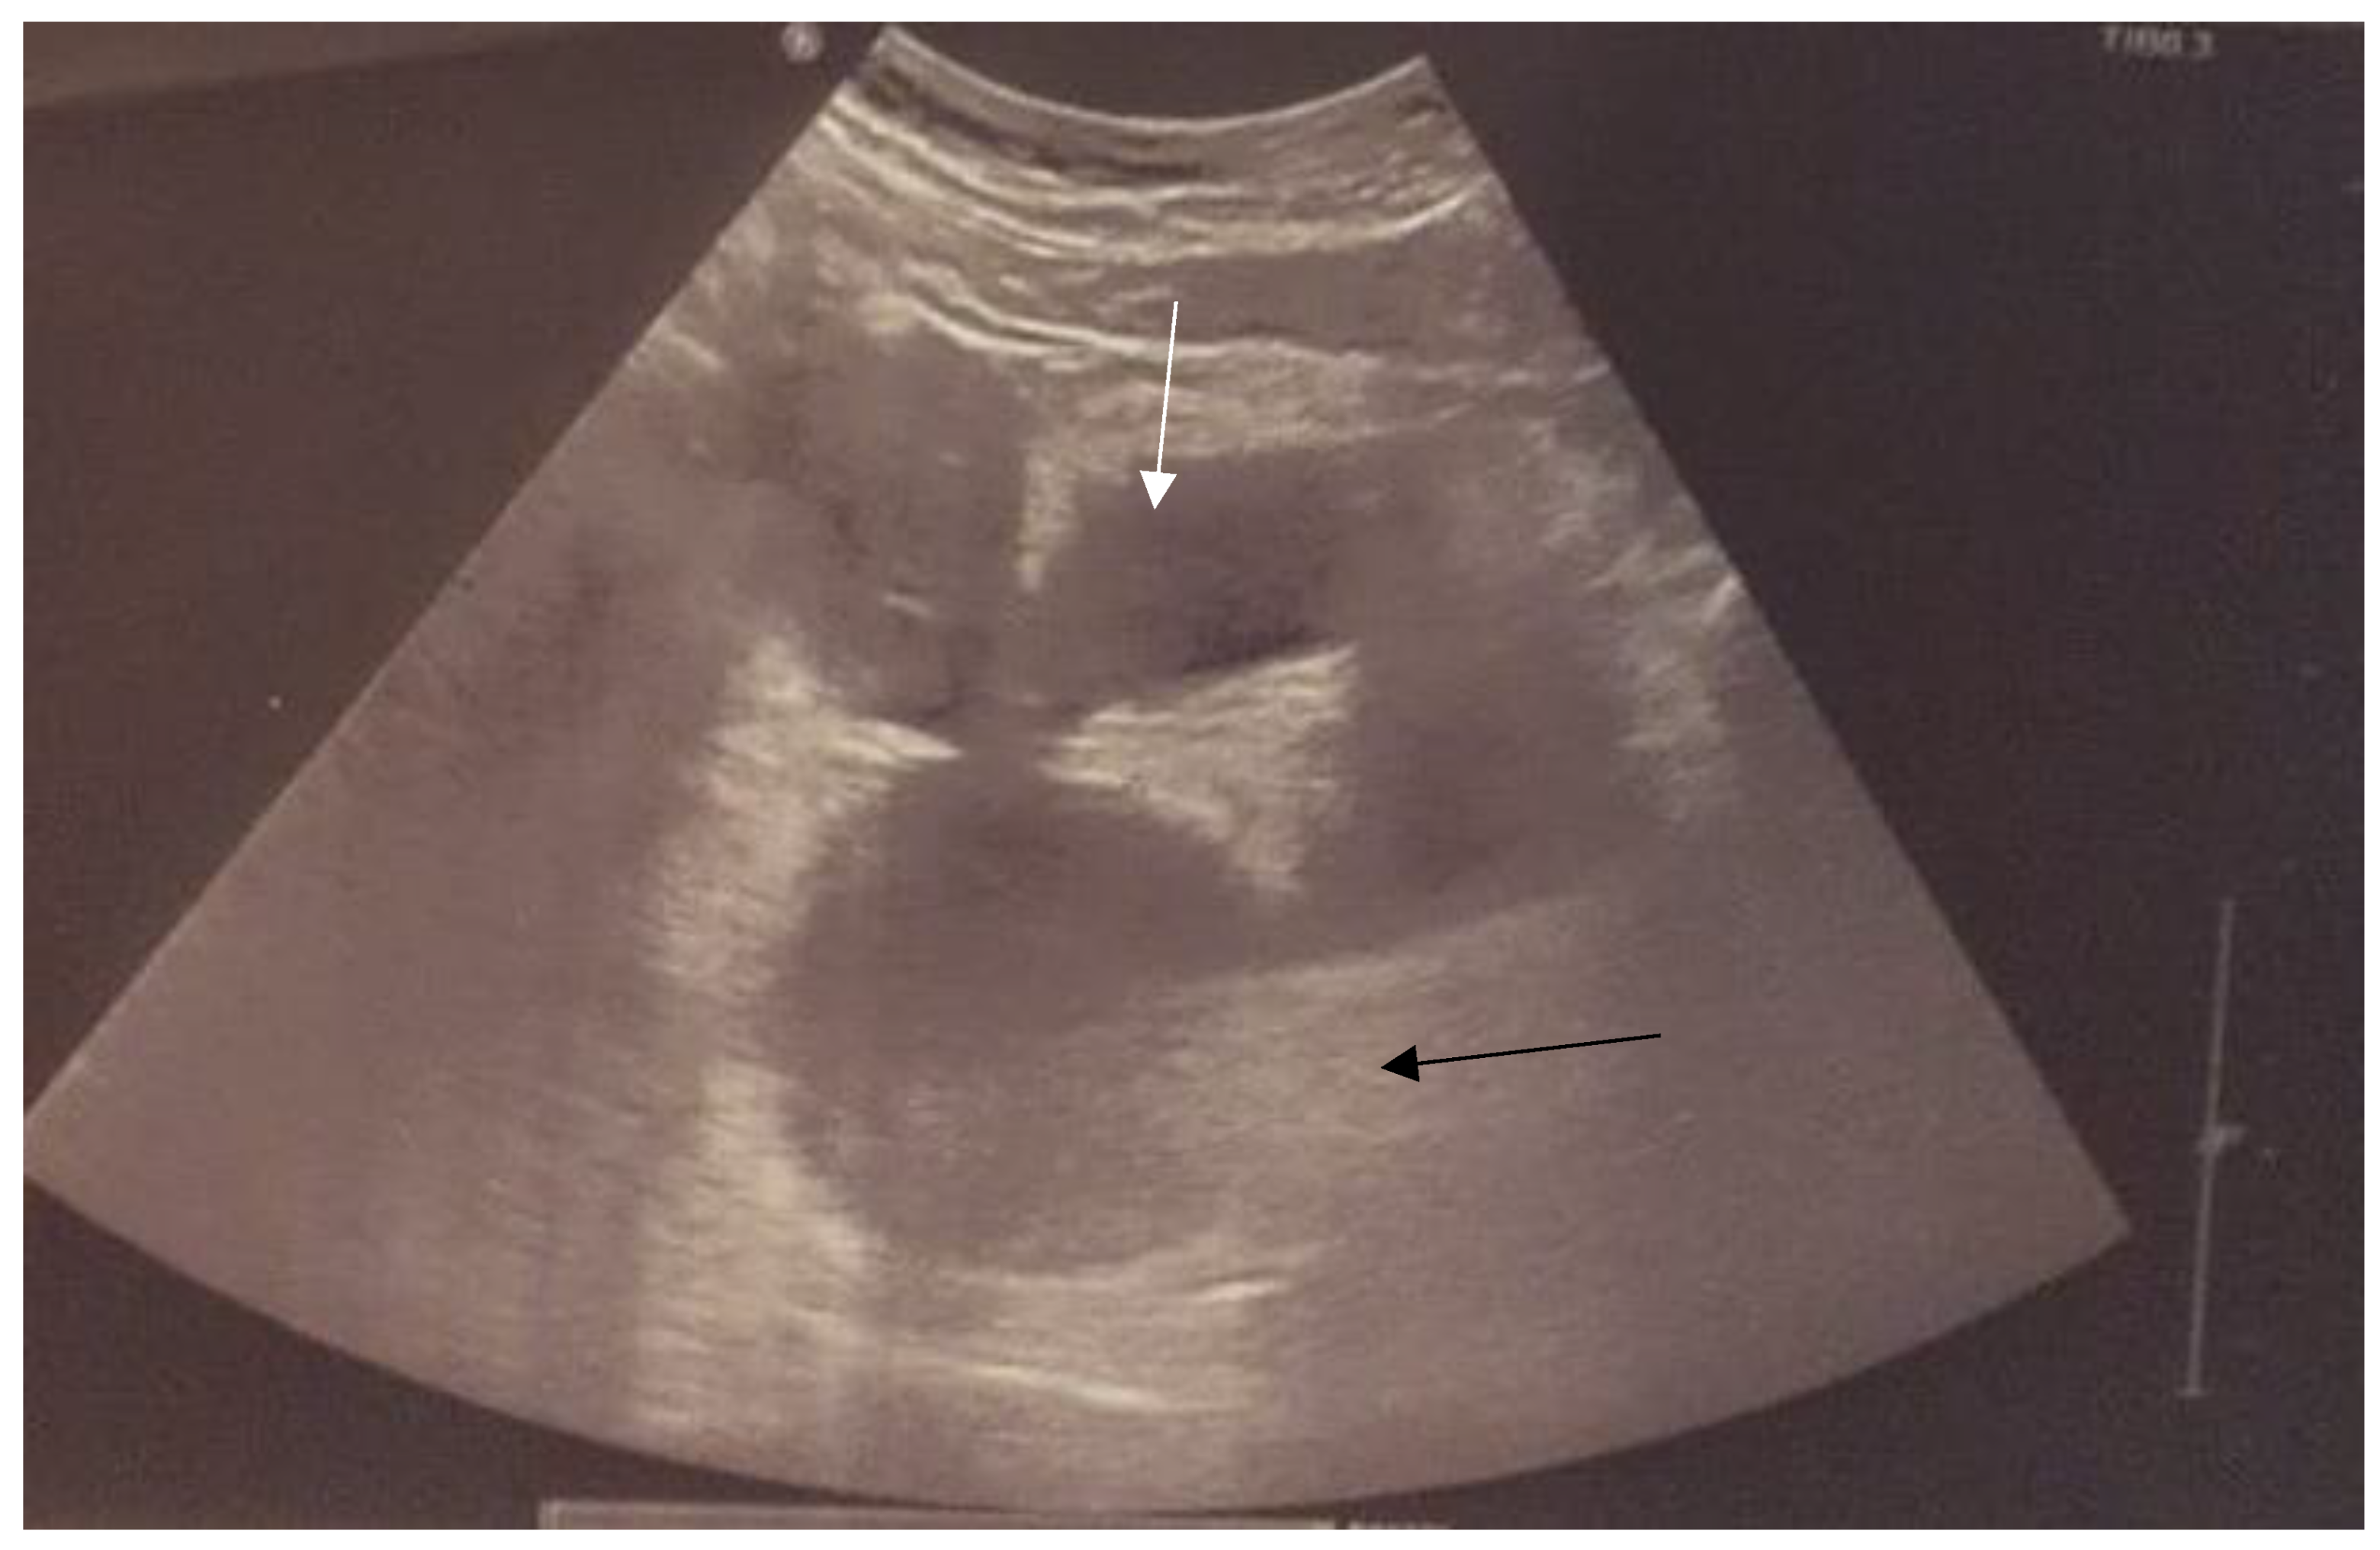

Step 1. Preoperative management Patients age (mostly occurs in young females), accurate history: time of first period, gradually increased symptoms, the appearance of symptoms during menarche, symptoms increase with each subsequent period, recurrent UTI, urinary disorders [8,9]. Perform physical examination. Next to the transabdominal US, transperineal and transrectal US can be useful in emergency situations to accurately access the place of abnormality [10]. MRI imaging should be considered as "gold standard in the diagnostic process [11]. Plan of the surgery and step by step proceeding is important while operating patients with urogenital abnormalities. As interdisciplinary collaboration of urologist and gynecologist is often necessary to treat correctly these patients. |